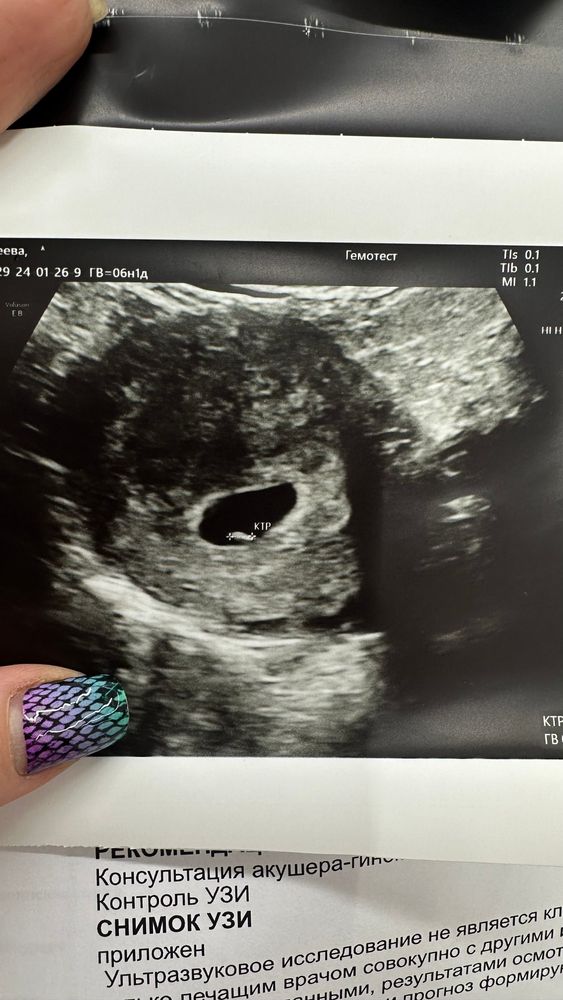

6 недель, полет нормальный

26.01.2024